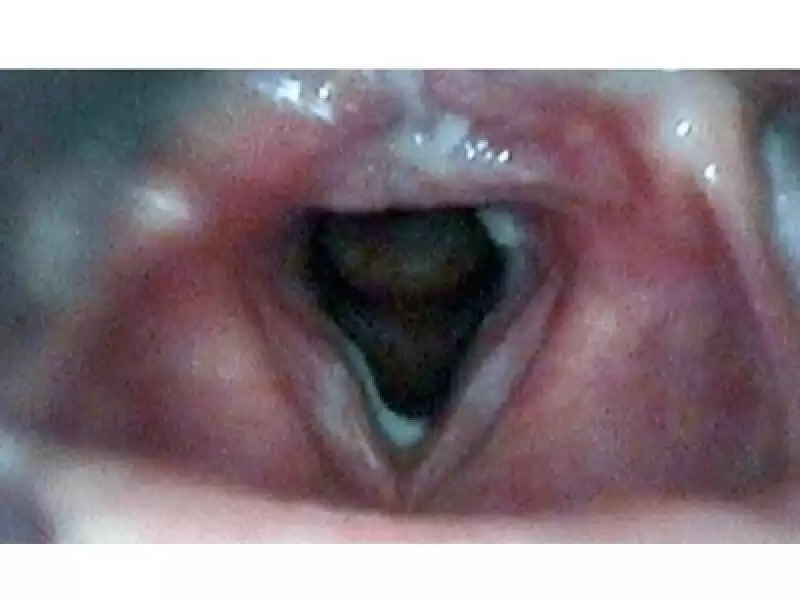

Baş ve boyun bölgesinde şişlik fark eden her yaşta birey öncelikle bir Kulak Burun Boğaz Hastalıkları – Baş ve Boyun Cerrahisi Uzmanı’na başvurmalıdır. Kulak Burun Boğaz Uzmanı yapacağı kapsamlı kulak, burun, boğaz ve tam bir baş boyun muayenesinin ardından (bu muayene hastanın gereksinimleri doğrultusunda genellikle geniz, yutak, gırtlak ve yemek borusu girişinin endoskopik olarak muayenesini de kapsar) gerekli bilgileri hastaya verecektir.